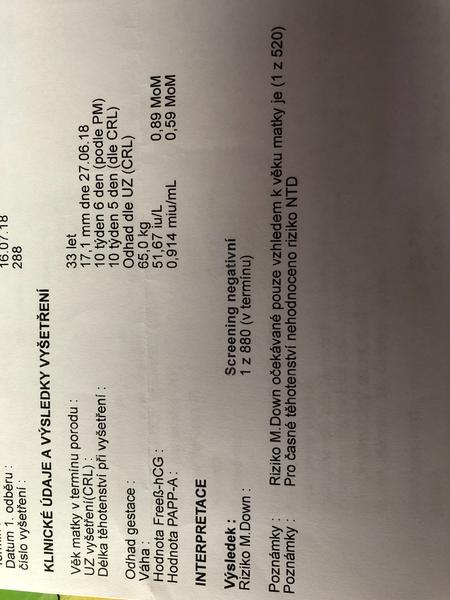

@seveneye mne ty hodnoty nic neříkají, posílám scan😉

@jednaholkaa já tam právě žádnou tu hodnotu volného Hcg nemám, jen to MoM

Ono se to zpřeházelo. Jsou tam vidět datumy.. 🙄

@jednaholkaa Tady jsem schválně našla ty výsledky z předchozích těhotenství 🙂 Obě to jsou holky 🙂 A hodnoty nízké 🙂 Teď zatím hodnoty nevím, na screening jdu ve čtvrtek :D